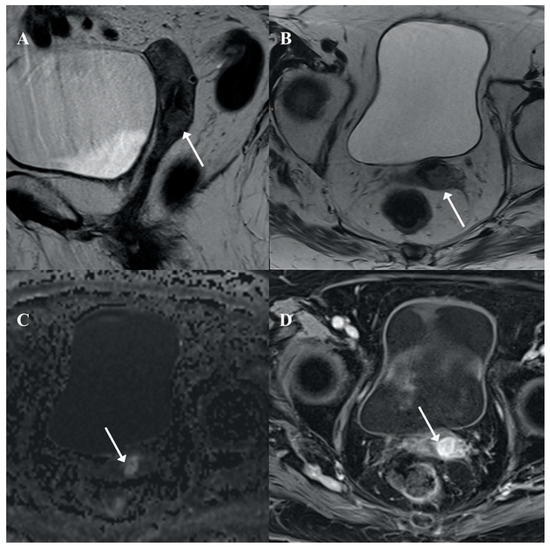

2. Case Report